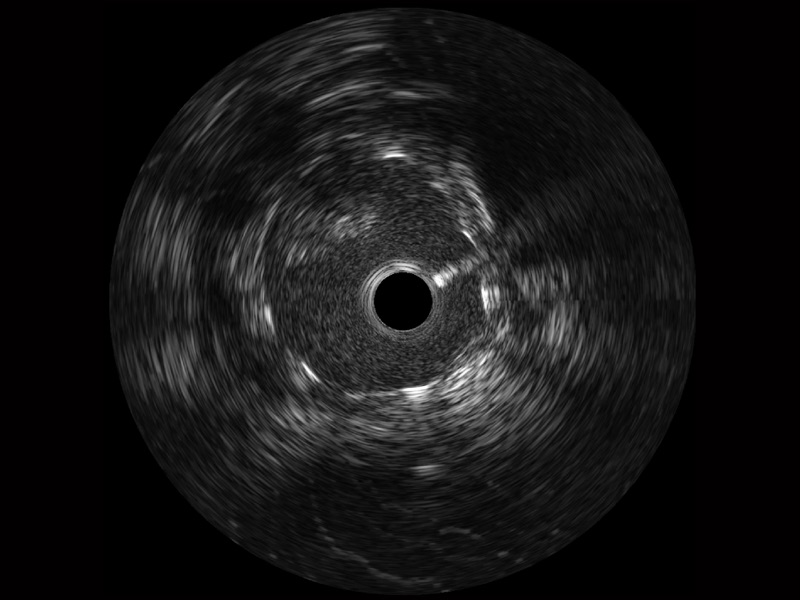

• 传统IVUS图像

对比传统IVUS导管成像,美狮贵宾会官网宽频IVUS图像的近场支架梁显影更细腻,远场中膜外血管仍清晰可辨,兼顾远中近,兼顾分辨力与穿透深度